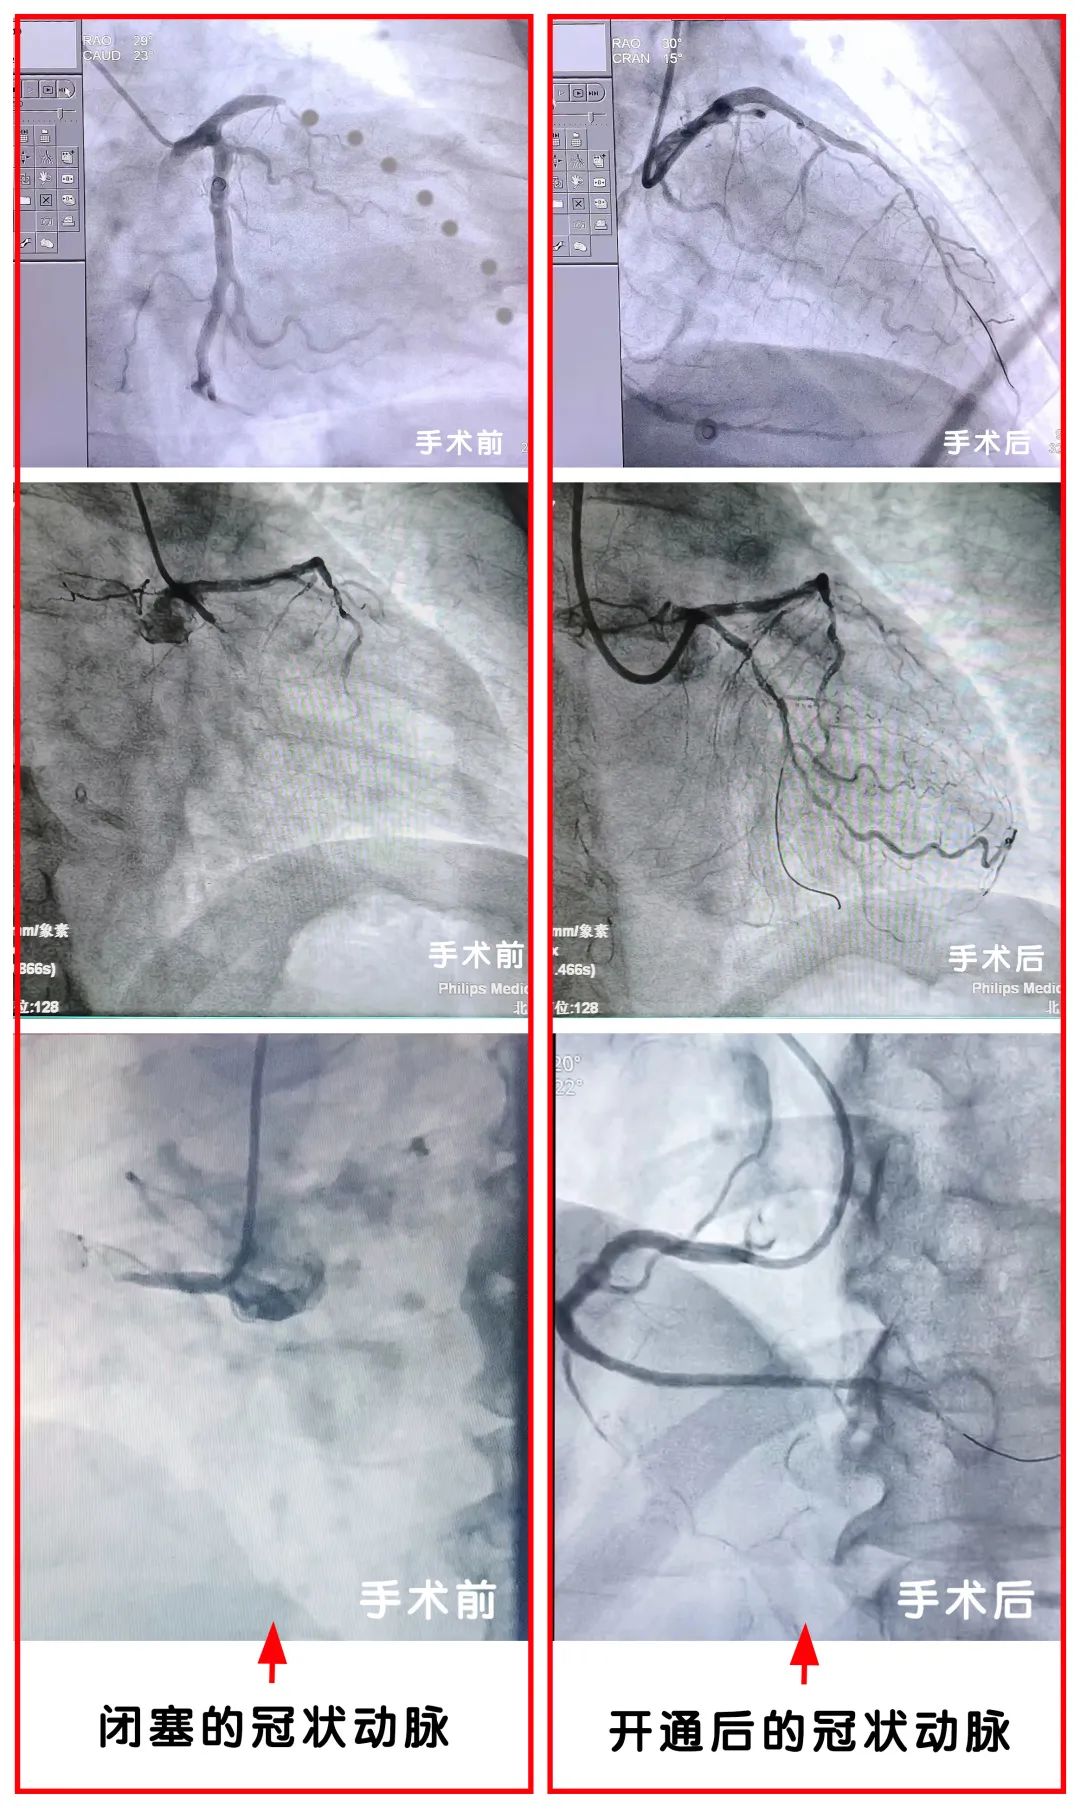

从急诊室接患者到介入中心,动脉穿刺,造影,确定罪犯血管,导丝通过病变,血管再灌注,血栓抽吸,心电图改变,患者症状减轻,一系列娴熟地操作,立竿见影的效果,给每一位参加急救的医护人员建立了极大的信心。

急性心肌梗死急诊PCI 术是指在急性心梗早期通过介入手段进行冠脉血运重建,使闭塞血管得以再通。急诊PCI手术是目前国际上公认的抢救心肌梗死病人最有效的治疗手段。该方法能减少心肌梗死的并发症,更有效地改善心肌梗死后的心脏功能,缩短住院时间、降低致残率和致死率。

急诊PCI对于急性心肌梗死再次建立冠状动脉灌注是一个非常有效的方法,为患者开辟了一条生命绿色通道。相信未来,在医院高质量发展的新征程上,在兄弟科室的支持和鼓励下,北京老年医院心血管急诊PCI团队,将不断完善胸痛中心建设,创造更多的生命奇迹。